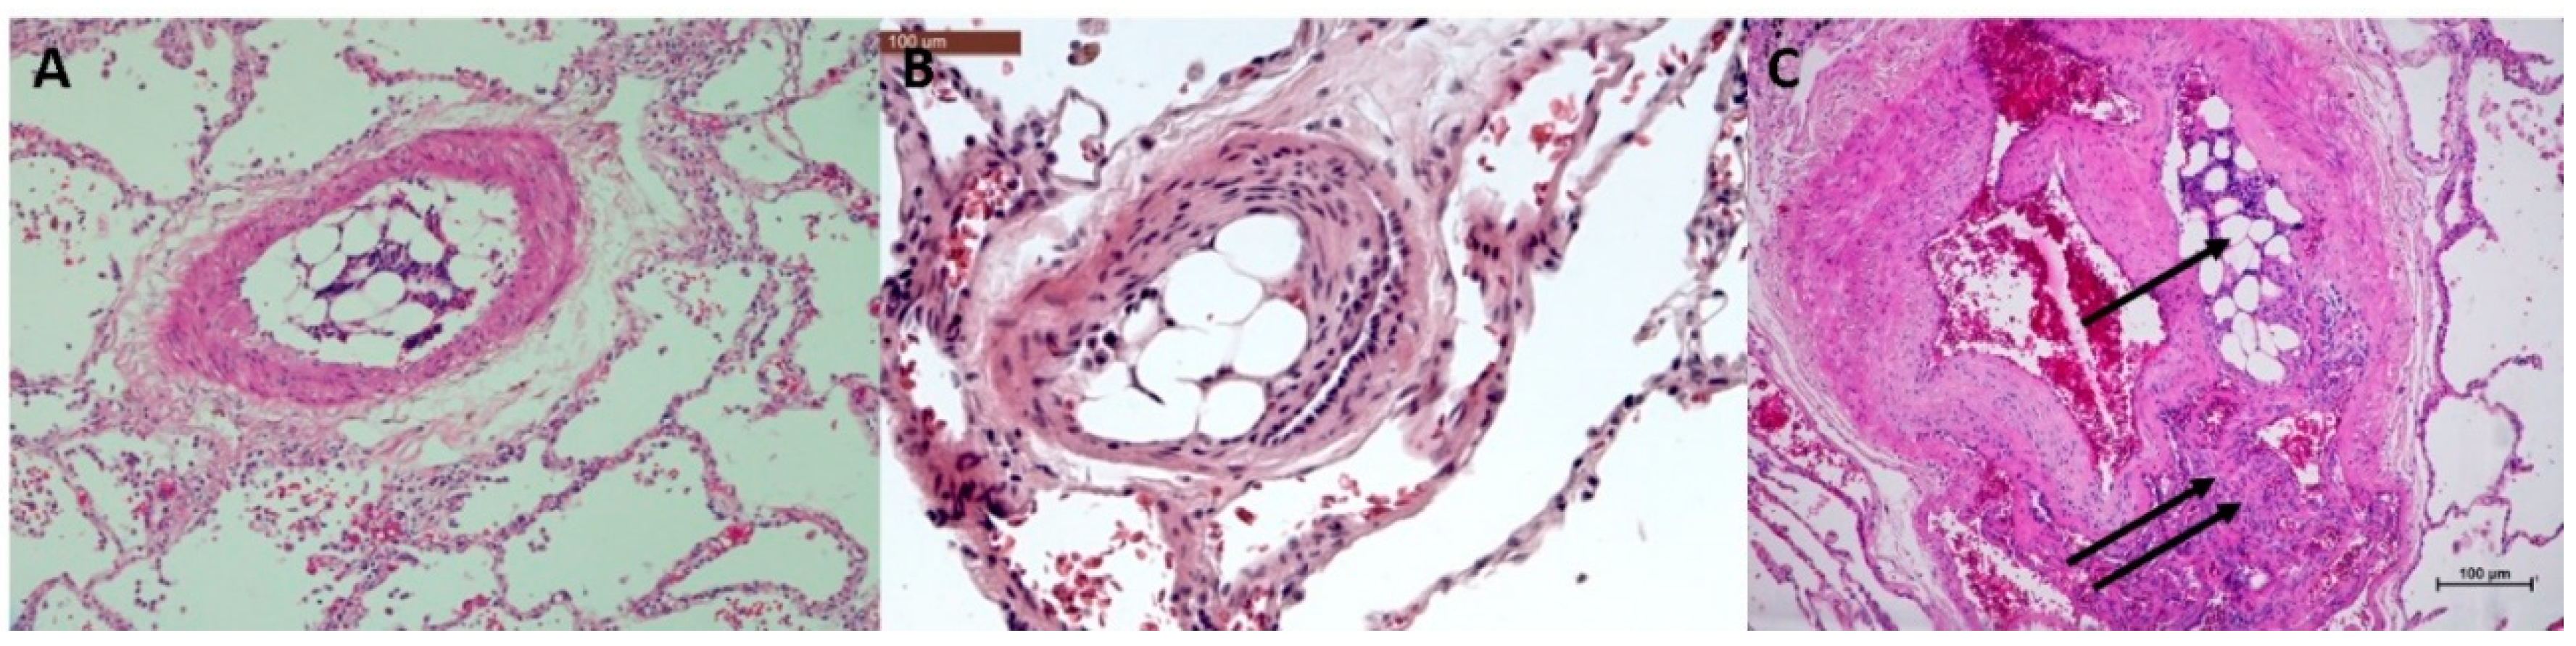

3.3. Histopathology of Pulmonary Angiophagy in Human Samples